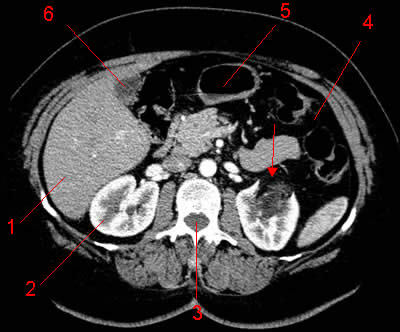

Diagnostic? Quelle maladie héréditaire peut favoriser ce genre de lésion surtout si bilatérales?

Angiomyolipome du rein gauche reconnaissable à sa composante graisseuse.

La Sclérose Tubéreuse de Bourneville donne des agniomyolipomes bilatéraux